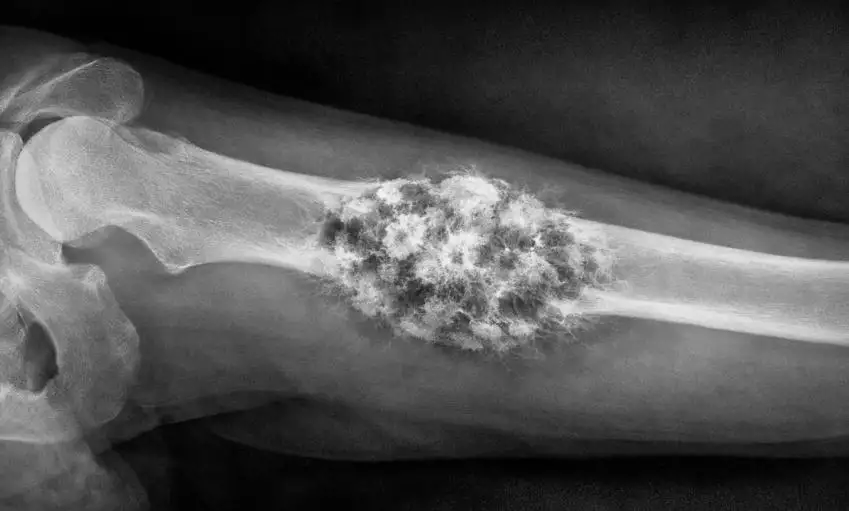

Luusyöpä olkapäässä: Oireet, diagnosointi ja nykyaikaiset hoitovaihtoehdot

Luusyöpä olkapäässä on harvinainen mutta vakava sairaus, joka voi vaikuttaa…

Osteosarkooma Luusyöpä: Oireet, Hoito, Ennuste ja Uusimmat Hoitomenetelmät

Osteosarkooma luusyöpä on harvinainen mutta vakava syöpämuoto, joka saa alkunsa…

Luusyöpä reisiluussa – oireet, hoito ja ennuste kattavasti selitettynä

Luusyöpä reisiluussa on harvinainen mutta vakava sairaus, joka voi vaikuttaa sekä nuoriin…